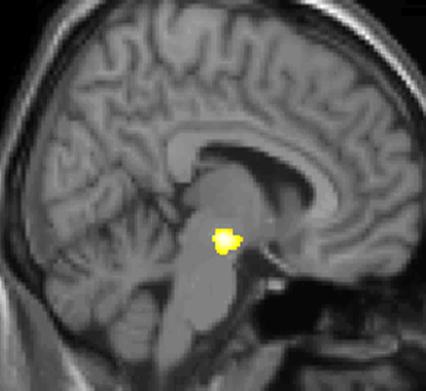

PET 스캔

PET 스캔에 의한, 군발 두통 발생 중에 활발해진 뇌 부분을 나타내는 그림.

양전자 방출 단층 촬영술(PET) 이미지 1: 통증 중 활성화되는 뇌 영역

실제로 양전자 방출 단층 촬영술(PET) 스캔 연구 결과, 군발 두통 발작 중에 통증이 없을 때와 비교하여 시상하부의 특정 영역이 활성화되는 것이 관찰되었다. 또한, 복셀 기반 형태 계측법(VBM)을 이용한 연구에서는 군발 두통 환자와 그렇지 않은 사람 사이에 뇌 구조를 비교했을 때, 시상하부의 일부 영역에서 구조적인 차이가 발견되기도 했다.[35] 이러한 영상 연구 결과는 시상하부가 군발 두통의 발생과 관련이 깊다는 가설을 뒷받침한다.